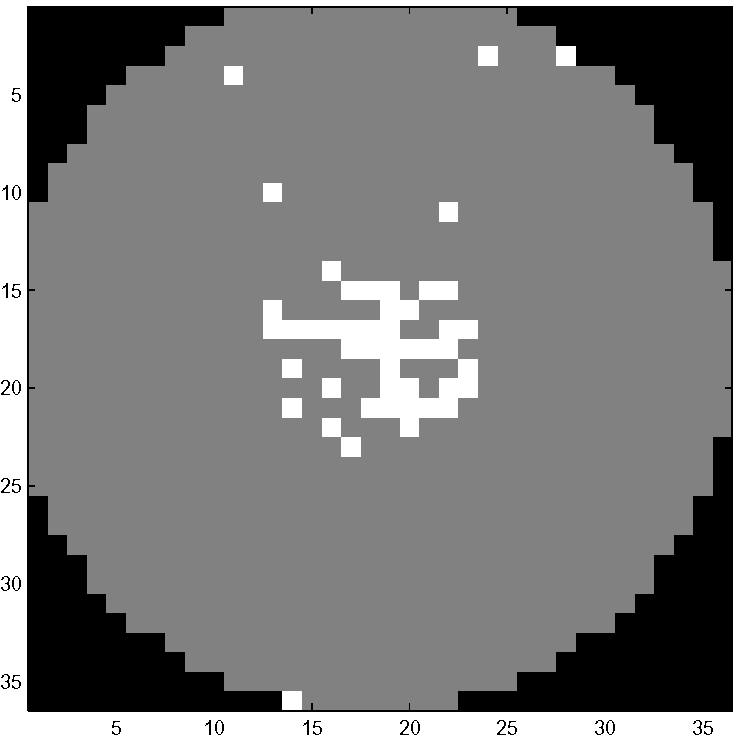

with the stimulus time-series (Fig. 5-left). The two parameters and were randomly distributed according to two uniform distributions, on and on respectively. The other parameters were fixed and chosen as follows, and . By varying and independently, we generated a family of hemodynamic responses with different peak dispersions and scales. We generated independent realizations according to this design. Each dataset consisted of a white disk of activated voxels inside a circular gray brain of background voxels (Fig. 5-left). Black voxels were in the air. There were altogether voxels inside the circular brain, with activated

voxels, ( activation). Fig. 6-left shows the projections on the first two principal axes of the time series of one realization. The projections are color-coded according to their status: activated (red diamond) and background (black circle). The parameterization given by our approach is shown in 6-right. We used only coordinates in (8) for . Activated time series are distributed along a thin strip that extends outward from the main cluster. This low dimensional structure is compact and easy to identify. In comparison, the two dimensional representation given by PCA (Fig. 6-left) is less conspicuous: activated time series (red) overlap with background time series (black). After embedding the dataset into two dimensions, the dataset is partitioned into two clusters. Fig. 7-left shows the result of clustering: the labels (red for activated, black for background) are based on the clustering only. The corresponding activation map is shown in Fig. 7-right. We compared our algorithm with a linear model equipped with the perfect knowledge of the hemodynamic response (with and ). A Student -test was applied to the regression coefficient to test its significance, and voxels with a -value smaller than a threshold were considered activated. Fig. 8 provides a quantitative comparison